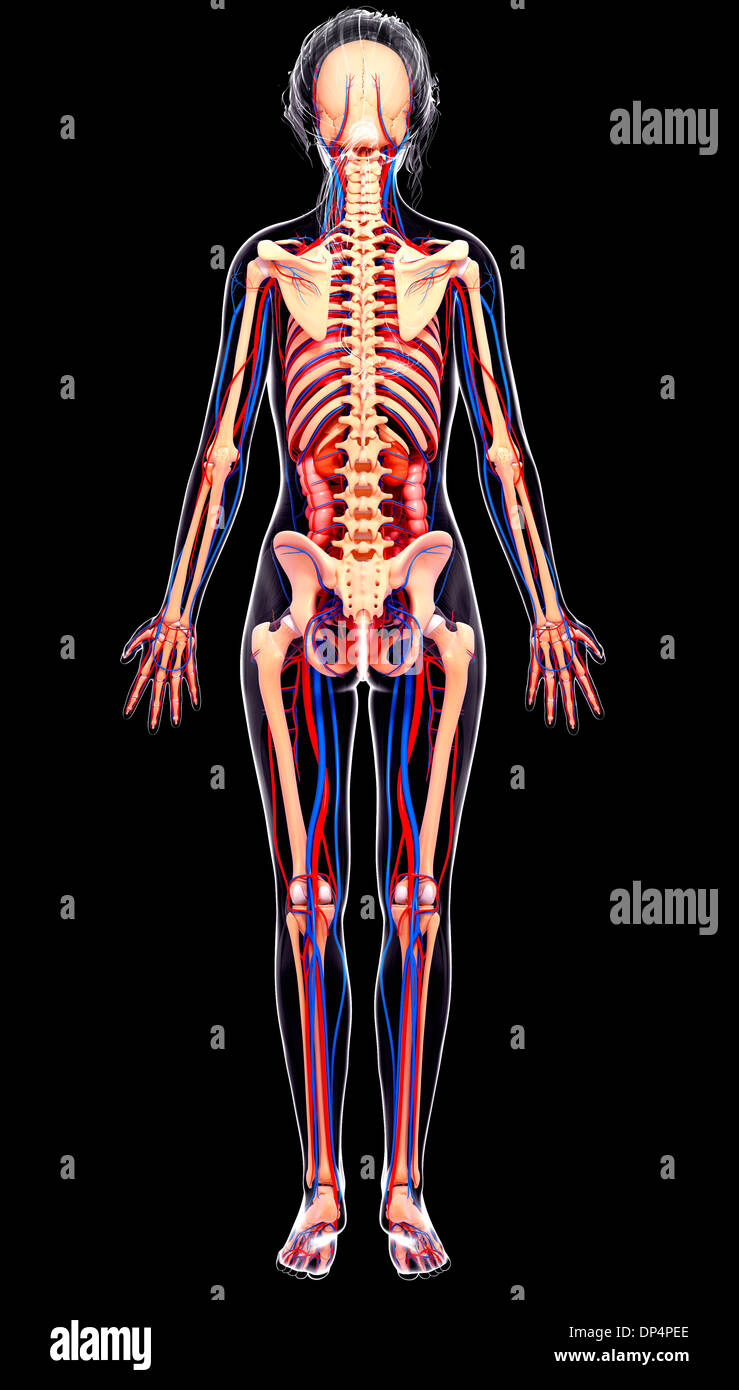

fineartamerica.comFemale Anatomy, Artwork Stock Photo - Alamy

fineartamerica.comFemale Anatomy, Artwork Stock Photo - Alamy

fineartamerica.comFemale Anatomy, Artwork Stock Photo - Alamy

fineartamerica.comFemale Anatomy, Artwork Stock Photo - Alamy

www.alamy.comFemale Anatomy, Artwork Stock Photo - Alamy

www.alamy.comFemale Anatomy, Artwork Stock Photo - Alamy

bocadowasubo.github.ioFemale Anatomy, Artwork Stock Photo - Alamy

bocadowasubo.github.ioFemale Anatomy, Artwork Stock Photo - Alamy

fineartamerica.comFemale Anatomy, Artwork Stock Photo - Alamy

fineartamerica.comFemale Anatomy, Artwork Stock Photo - Alamy

www.etsy.comFemale Anatomy, Artwork Stock Photo - Alamy

www.etsy.comFemale Anatomy, Artwork Stock Photo - Alamy

www.alamy.comFemale Anatomy, Artwork Stock Photo - Alamy

www.alamy.comFemale Anatomy, Artwork Stock Photo - Alamy

www.alamy.comFemale Anatomy, Artwork Stock Photo - Alamy

www.alamy.comFemale Anatomy, Artwork Stock Photo - Alamy

fineartamerica.comFemale Anatomy, Artwork Stock Photo - Alamy

fineartamerica.comFemale Anatomy, Artwork Stock Photo - Alamy

Female Anatomy, Artwork Stock Photo - Alamy

www.alamy.comFemale Anatomy, Artwork Stock Photo - Alamy

www.alamy.comFemale Anatomy, Artwork Stock Photo - Alamy

www.etsy.comFemale Anatomy, Artwork Stock Photo - Alamy

www.etsy.comFemale Anatomy, Artwork Stock Photo - Alamy

www.alamy.comFemale Anatomy, Artwork Stock Photo - Alamy

www.alamy.comFemale Anatomy, Artwork Stock Photo - Alamy

www.alamy.comFemale Anatomy, Artwork Stock Photo - Alamy

www.alamy.comFemale Anatomy, Artwork Stock Photo - Alamy

Female Anatomy, Artwork Stock Photo - Alamy

www.alamy.com3d Rendered Illustration Of The Female Anatomy Stock Photo - Alamy

www.alamy.com3d Rendered Illustration Of The Female Anatomy Stock Photo - Alamy

fineartamerica.com3d Rendered Illustration Of The Female Anatomy Stock Photo - Alamy

fineartamerica.com3d Rendered Illustration Of The Female Anatomy Stock Photo - Alamy

pixels.comFemale Anatomy, Artwork Stock Photo - Alamy

pixels.comFemale Anatomy, Artwork Stock Photo - Alamy